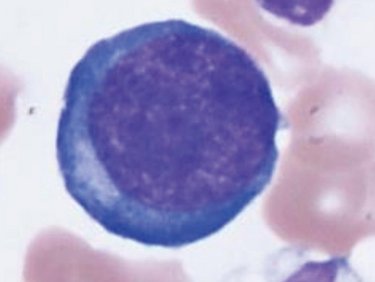

赤血球

成熟赤血球

未熟赤血球

赤血球系の異常